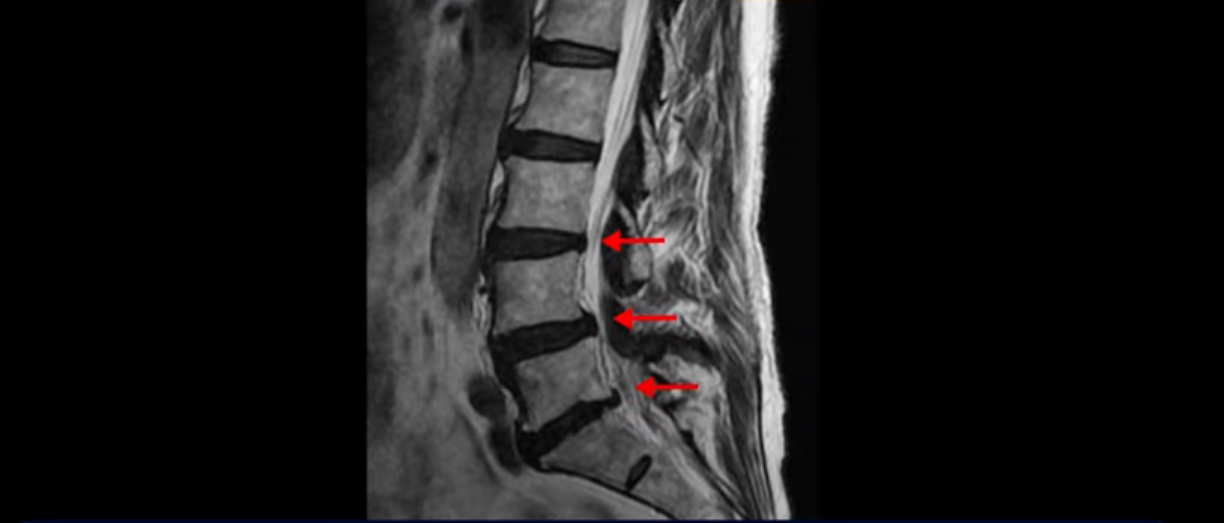

이분 MRI 보면서 설명드린 후 왜 이분처럼 발병한지 얼마 안된 협착증이 치료가 정말 빠르고 쉬운 건지 또 치료는 어떻게 하는 건지 자세히 설명 드리도록 하겠습니다.

MRI를 보면 척추 여러 마디가 퇴행되어 있고

척추관도 좁아져 있고

특히 왼쪽 신경가지가 빠져나가는 4번 5번, 5번 1번 추간공들이 많이 좁아져 있습니다.

그래서 이분은 몇 달 전부터 갑자기 왼쪽 엉덩이부터 발바닥까지 저리고 아픈 증상이 생겨서 걷기도 어렵고 무릎도 차고 시립니다. 그런데 왜 이렇게 얼마 전에 갑자기 발병한 협착증일수록 치료가 정말 빠르고 쉽다는 걸까요?

이분이 처음 아프게 된 건 작년 말입니다. 그런데 만일 이분이 아프기 전인 작년 초에 MRI를 찍었다면 지금 보시는 MRI와 많이 다를까요? 정답은 거의 차이가 없다입니다. 노화로 인해 신경 구멍이 좁아진 건 이미 오래 전에 벌어진 일입니다. 이렇게 신경 구멍이 좁아져 있는 채로 아무런 증상을 느끼지 않고 최소 5년에서 10년 이상 잘 산 것입니다. 이런 걸 잠복 협착이라고 합니다. MRI로 협착이 보이지만 아무런 증상이 없다는 뜻입니다.